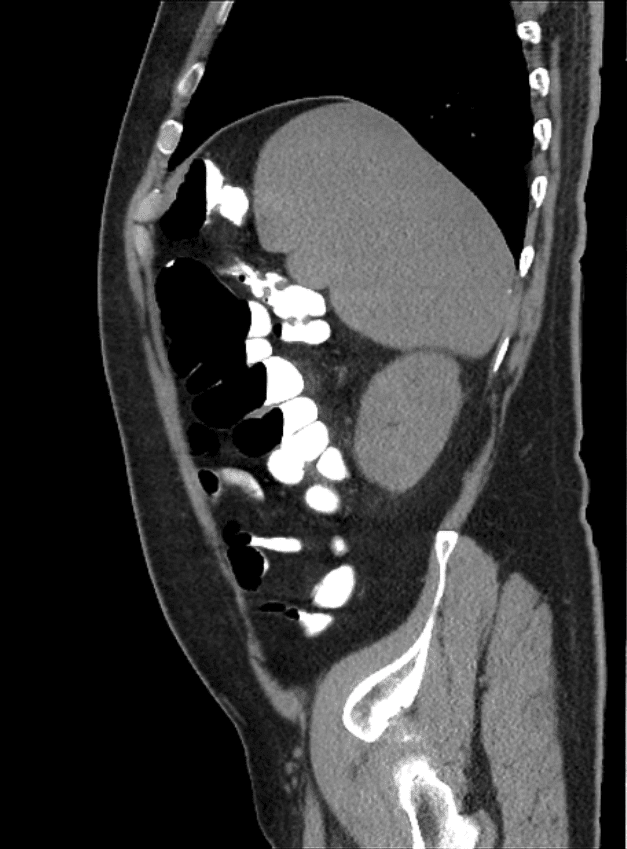

Chilaiditi

» Thông tin: Nam giới – 48 tuổi.

» Lâm sàng: Đau mạn sườn phải 1 tháng.